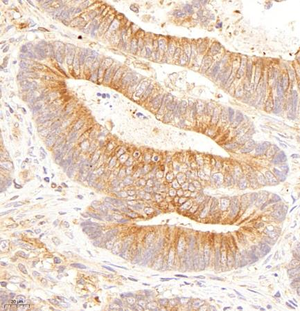

Immunohistochemistry analysis of paraffin embedded human renal carcinoma using P-α-tubulin (GB14162) at dilution of 1: 200 |